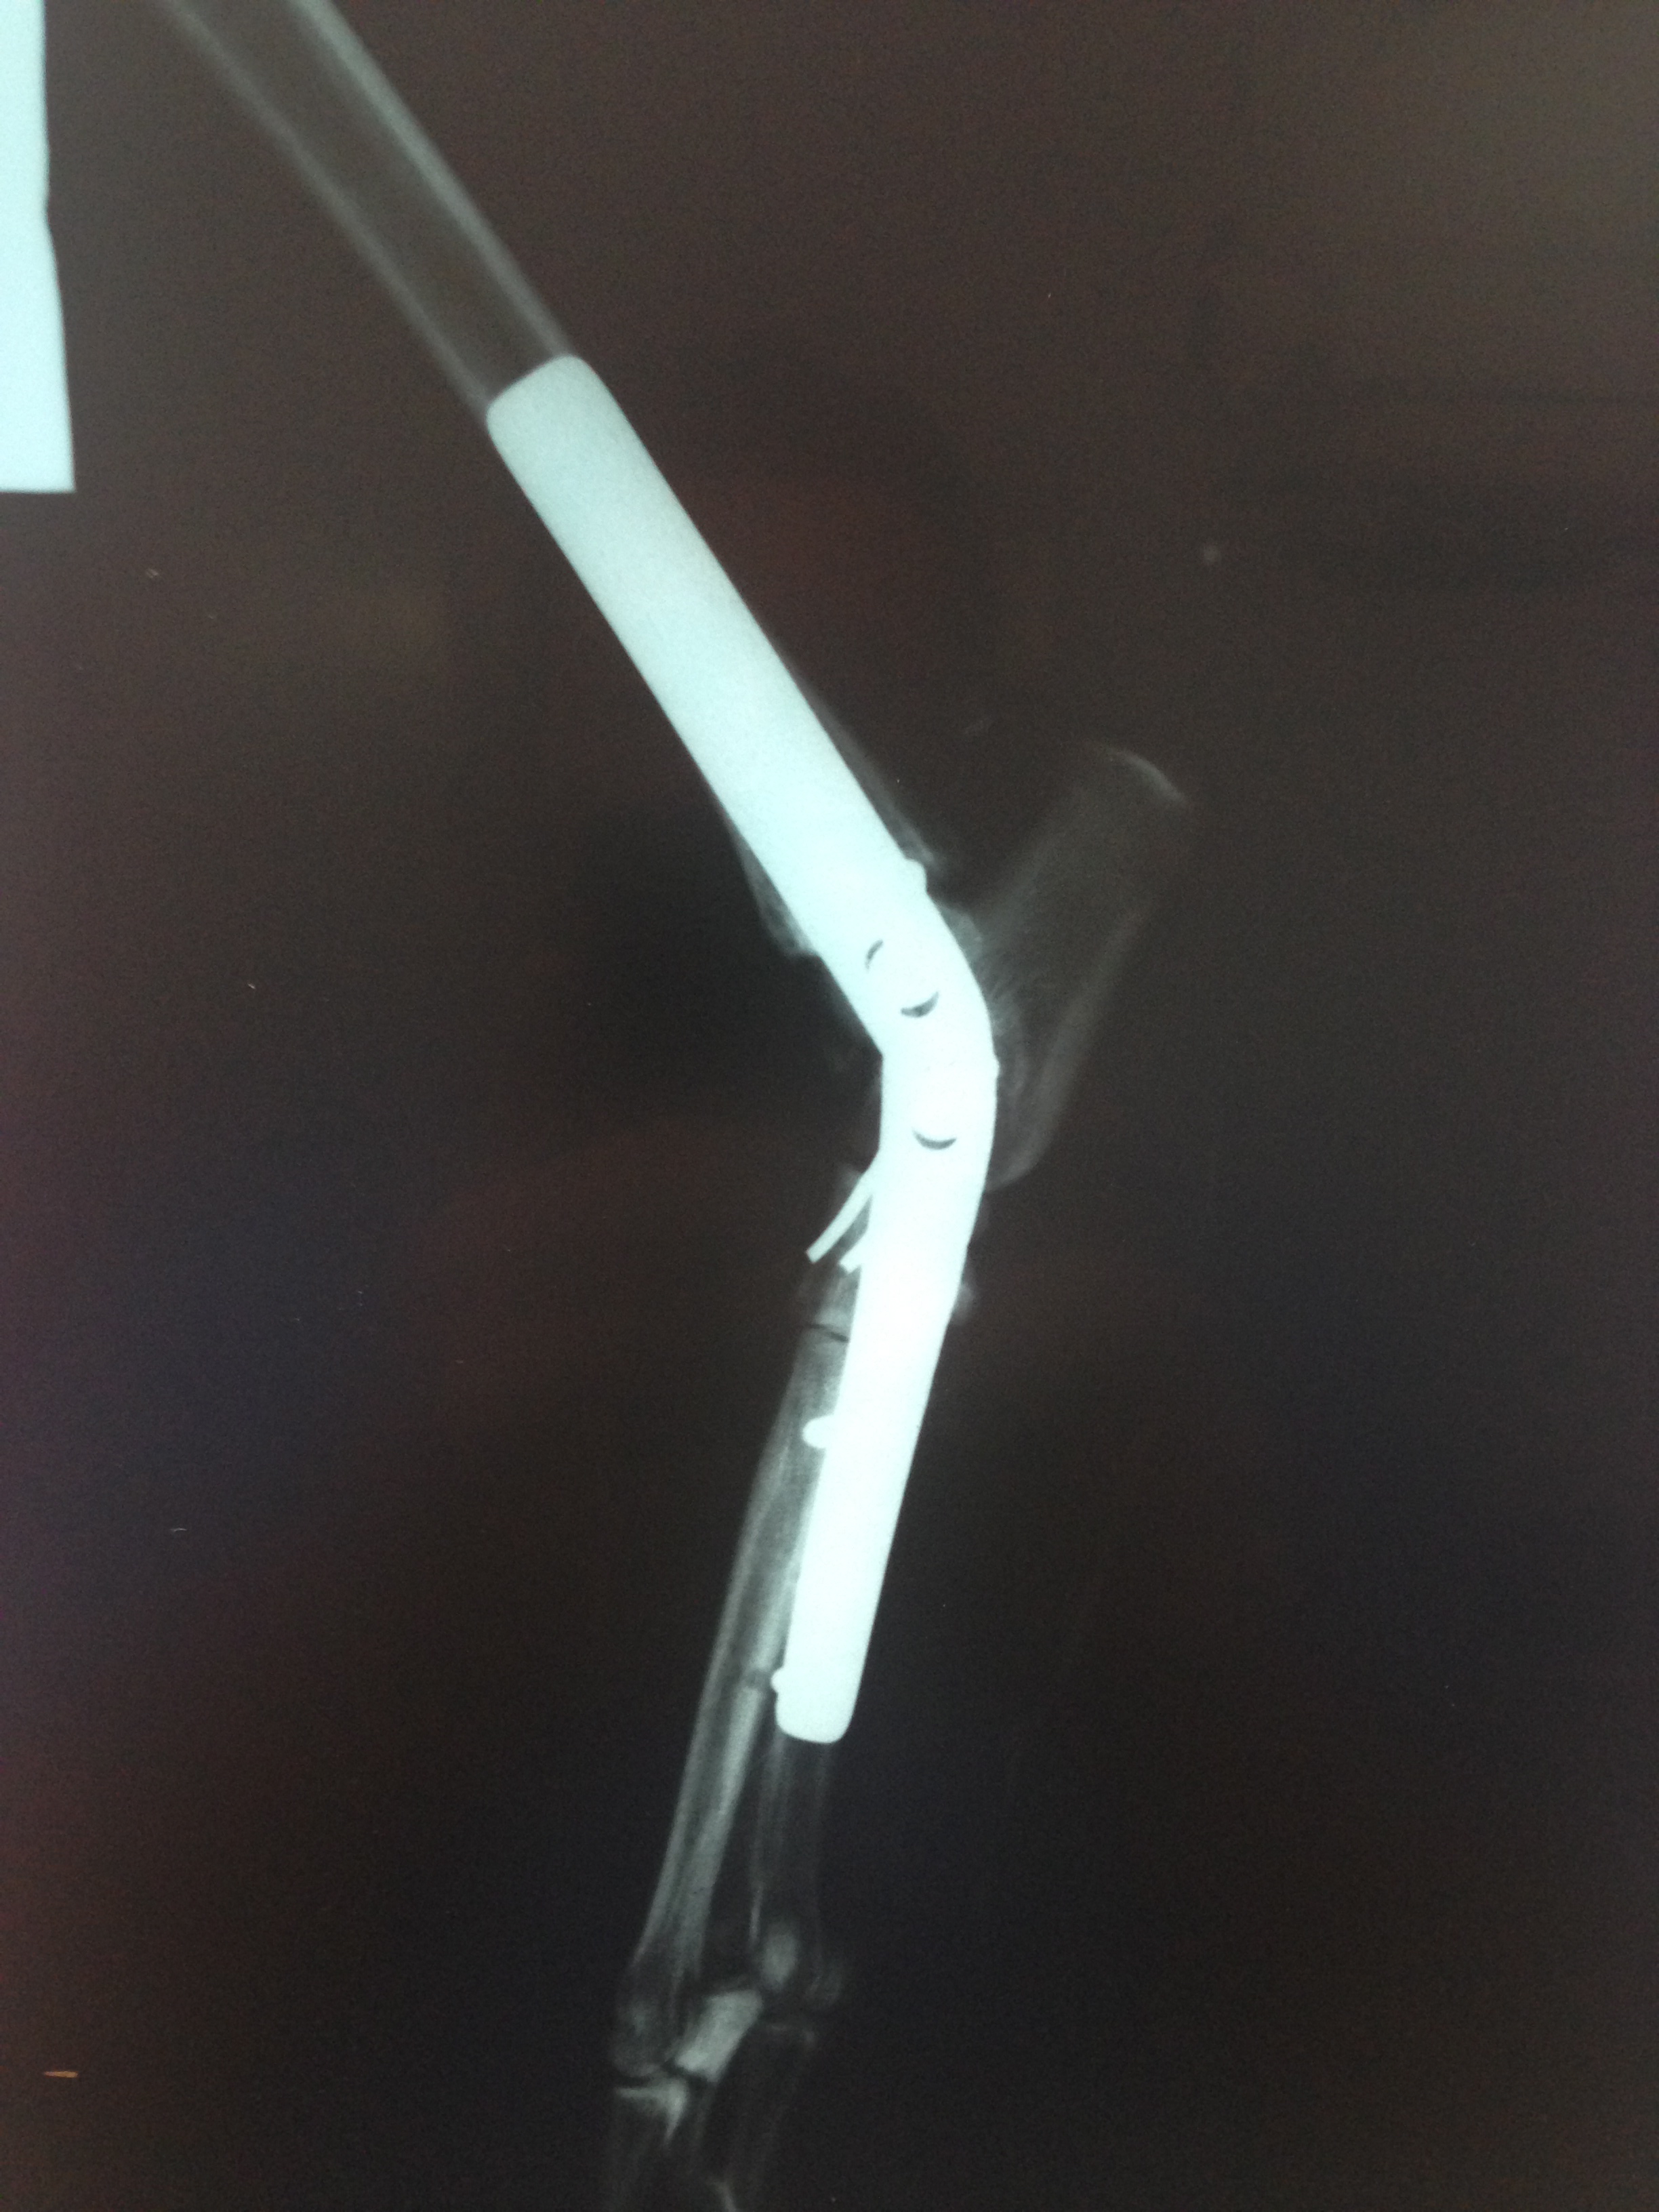

Casos Interessantes > ARTRODESE Tíbio-Tarsica por placa medial

Veja algumas Fotos